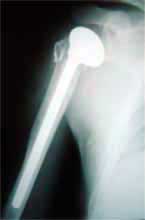

在肱骨近段有骨缺损、解剖标志失去时,首先保证假体的

正确旋后和插入的深度,在肱骨近端钻孔穿粗的不吸收缝线

• 大结节用粗的不吸收缝线,固定到假体的颈部

• 骨块位于假体领的下方且无很大张力